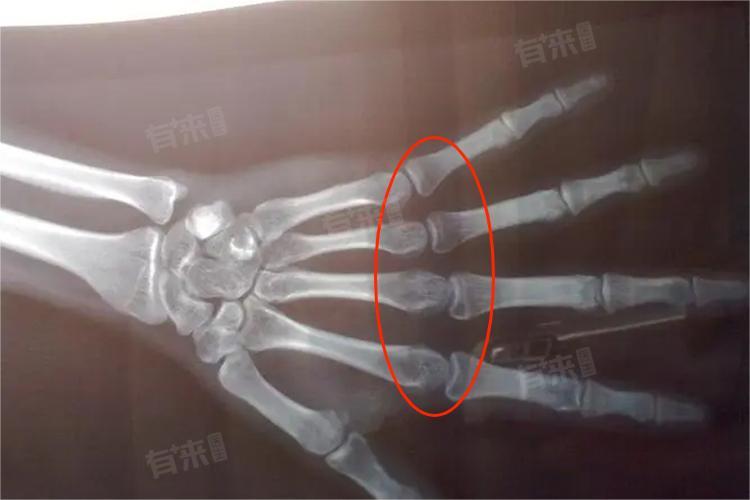

3、X光检查:通过X光片可以清晰地观察到骨骺线的状态,是判断骨骺线是否闭合最准确的方法。X光检查需要专业医生进行解读和分析,切勿自行判断。